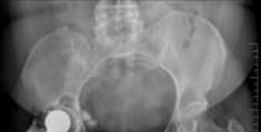

Advanced osteoarthritis bilaterally. Osteonecrosis and complete obliteration of the joint space on both sides…